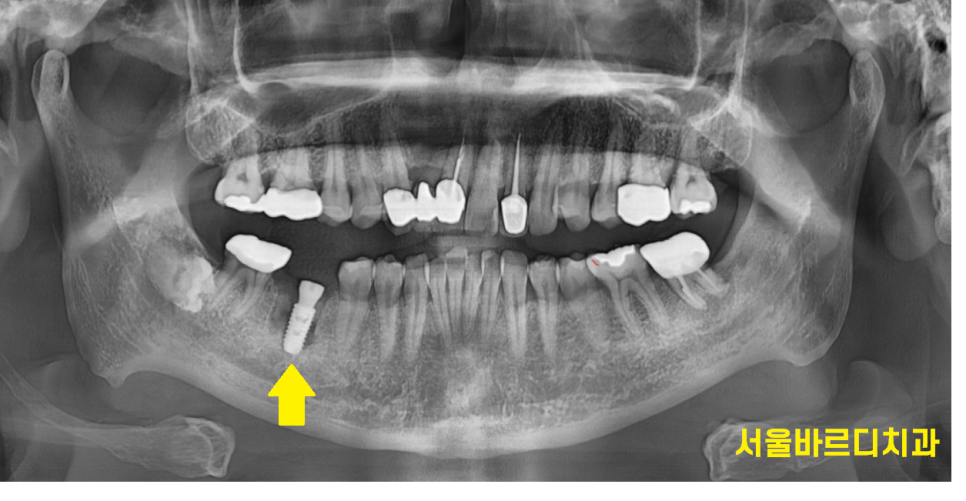

문제의 치아는 발치 후

염증을 깨끗하게 제거해주었습니다.

임플란트 식립 한 시간보다

염증 제거한 시간이 길 정도로

최대한 고름을 긁어내고

깨끗하게 만들어주었습니다.

염증이 남아있으면 임플란트에도 좋지 않기 때문이죠~

240208

염증이 있던 부위라

임플란트 골유착이 잘될 때까지 충분히 기다려주었습니다.

ct 상에서 임플란트 주변으로 잇몸뼈가 잘 찬 것을 확인후

머리를 만들어 주었어요